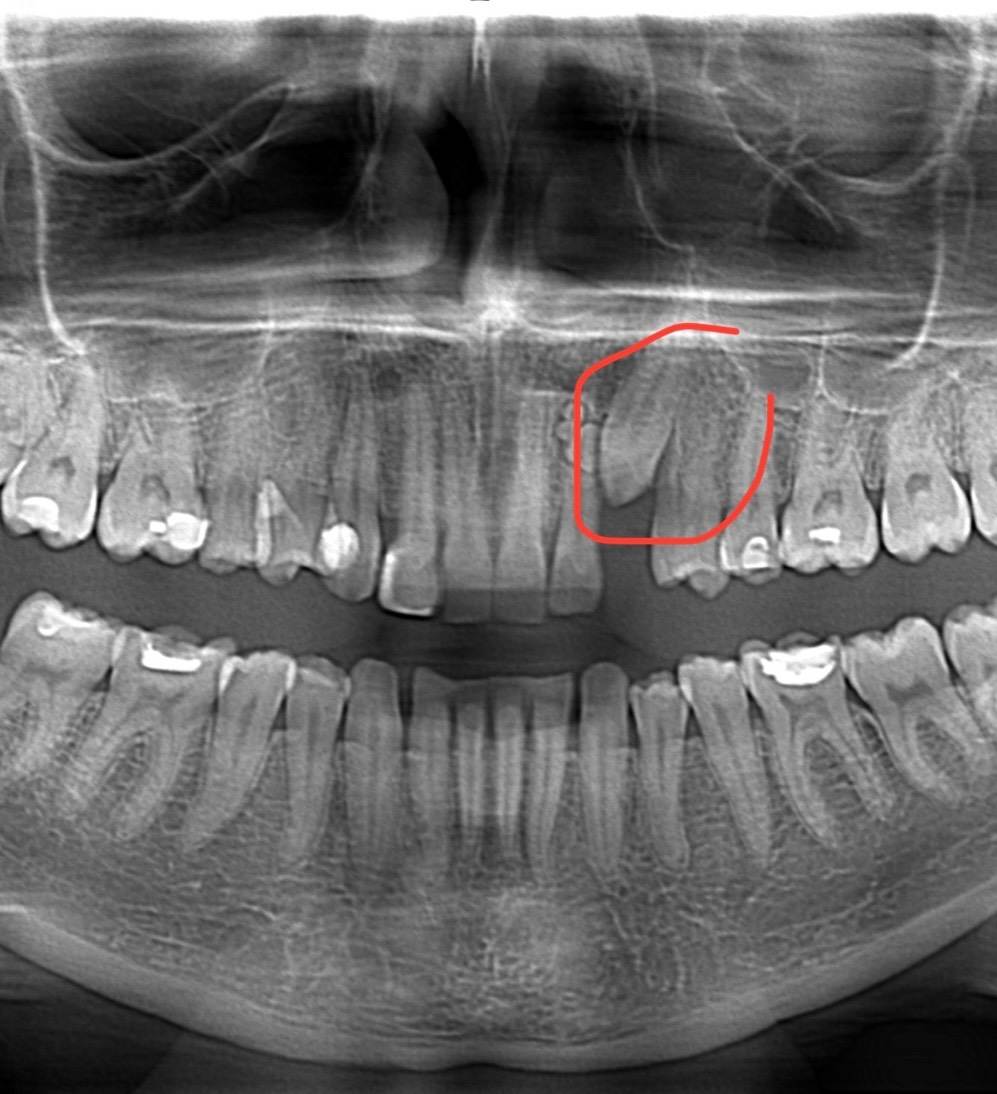

Дентальная галерея: ретинированный зуб клык и его лечение

Раздел: Компас решений